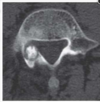

The axial noncontrast head CT (obtained for unrelated reasons) shown from an affected neonate results from which of the following

deformities?

a. Metopic synostosis

b. Unicoronal synostosis

c. Bicoronal synostosis

d. Lambdoid synostosis

e. Sagittal synostosis

Metopic synostosis